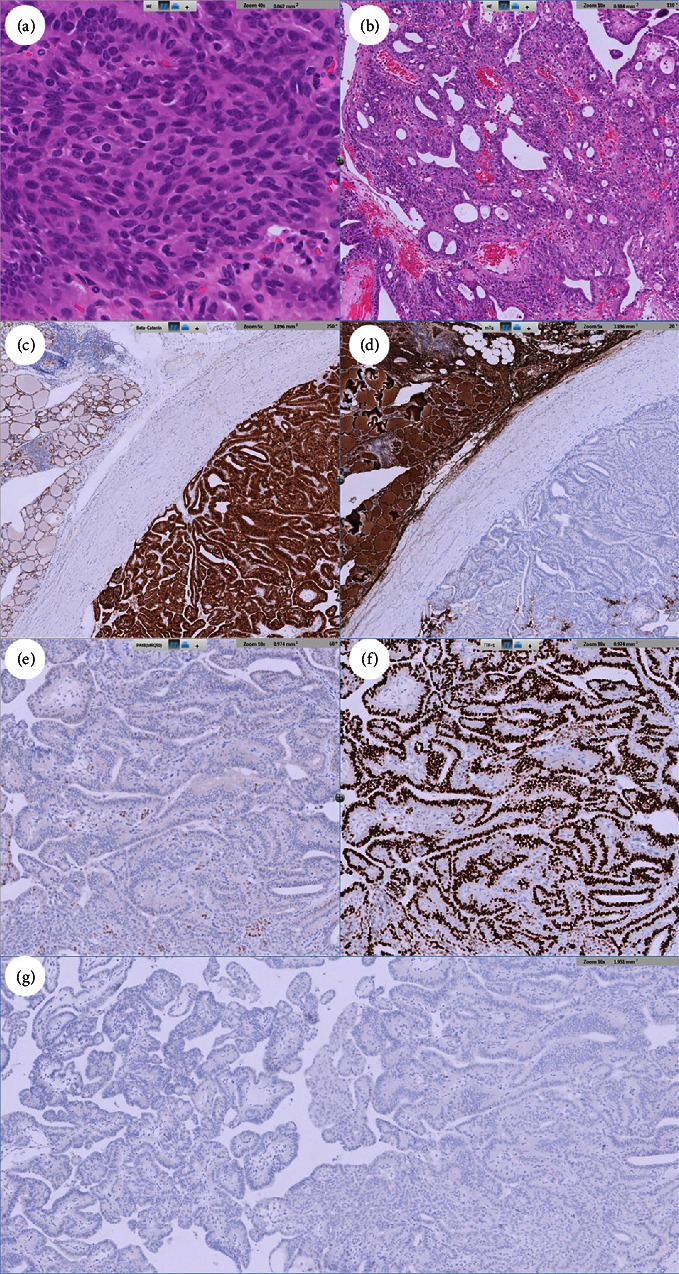

Results: A 31-year-old woman was found to have a thyroid nodule at the left lobe measuring 11.8 × 10.2 × 12.4 mm. Ultrasonography indicated a hypoechoic, solid nodule with regular margins. Cytology revealed a papillary structure of tall cells, leading to a PTC diagnosis. Nevertheless, the genetic analysis failed to detect mutations such as BRAF V600E, NRAS Q61R, NRAS Q61K, HRAS Q61R, or HRAS Q61K mutation or the fusion of CCDC6-RET, NCOA4-RET, PAX8-PPARG, ETV6-NTRK3, TPM3-NTRK1, IRF2BP2-NTRK1, or SQSTM1-NTRK1 in the aspirated follicular cells. The patient subsequently underwent total thyroidectomy with central lymph node dissection. Pathological examination revealed a cribriform pattern of spindle-shaped cells with morular areas. Immunohistochemical staining showed positive results for β-catenin and TTF-1, except in the morular regions, and negative results for PAX8, thyroglobulin, and BRAF (clone VE1). The diagnosis was confirmed to be cribriform morular thyroid carcinoma.

Conclusion: Significant cytological similarity exists between PTC and cribriform morular thyroid carcinoma. Preoperative genetic analysis is important to differentiate these two diseases. Cribriform morular thyroid carcinoma can be differentiated from common follicular-cell-derived tumors by the absence of typical mutations; the presence of nuclear and cytoplasmic expressions of β-catenin; the presence of TTF-1, except in morular areas; and the absence of thyroglobulin.